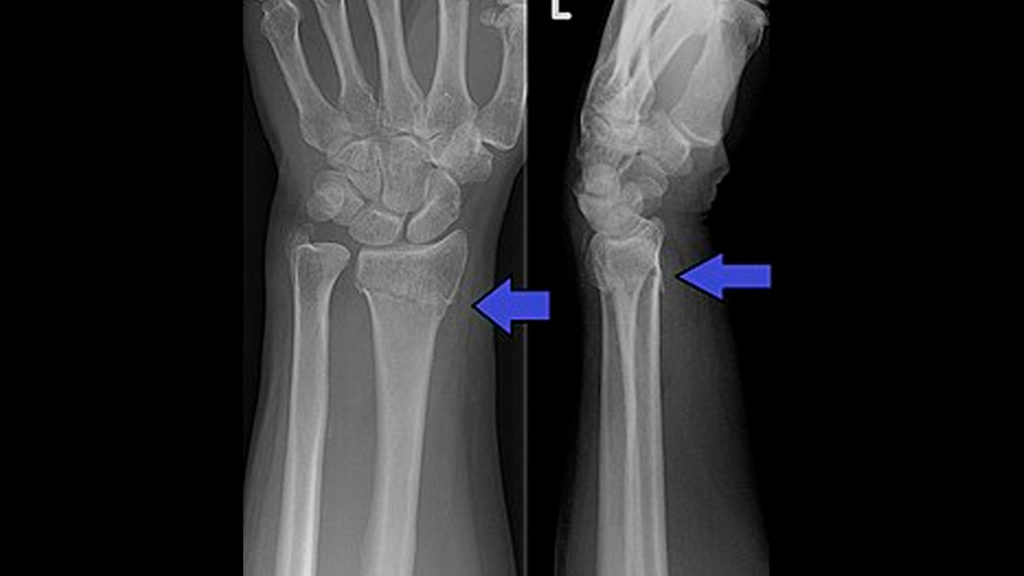

Son las imágenes para cada segmento anatómico sea diáfisis o zonas articulares del cuerpo, para determinar posibles lesiones como fracturas, luxaciones o artrosis.

*Rx. de antebrazo (radio y cúbito).